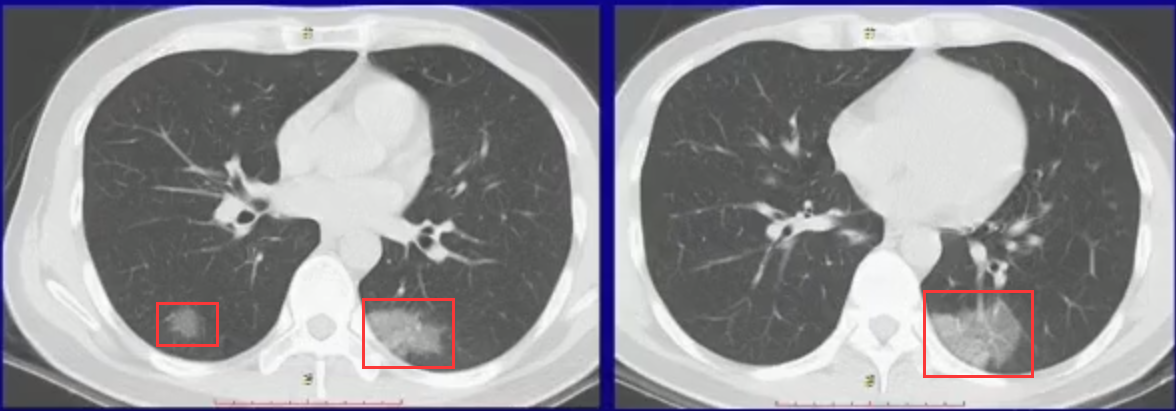

磨玻璃影

主要由于新冠病毒侵入并沿肺泡孔扩散引起磨玻璃影形成。这些变化包括导致 lung inflation, interstitial liquid leak, and septal thickening, 进而使得胸部 CT 显示密度增高呈白色。在病毒性感染中, 由于无细菌性渗出, 肺组织内仍充盈着空气, 因此通常不会出现实性改变(如 white patch), 而呈现模糊不清的磨玻璃影(blurred shadow)。通过观察磨玻璃影还可以观察到支气管(see Figure 1) (引用自广东省人民医院放射科行政副主任赵振军所做的主题报告)

图1.磨玻璃影